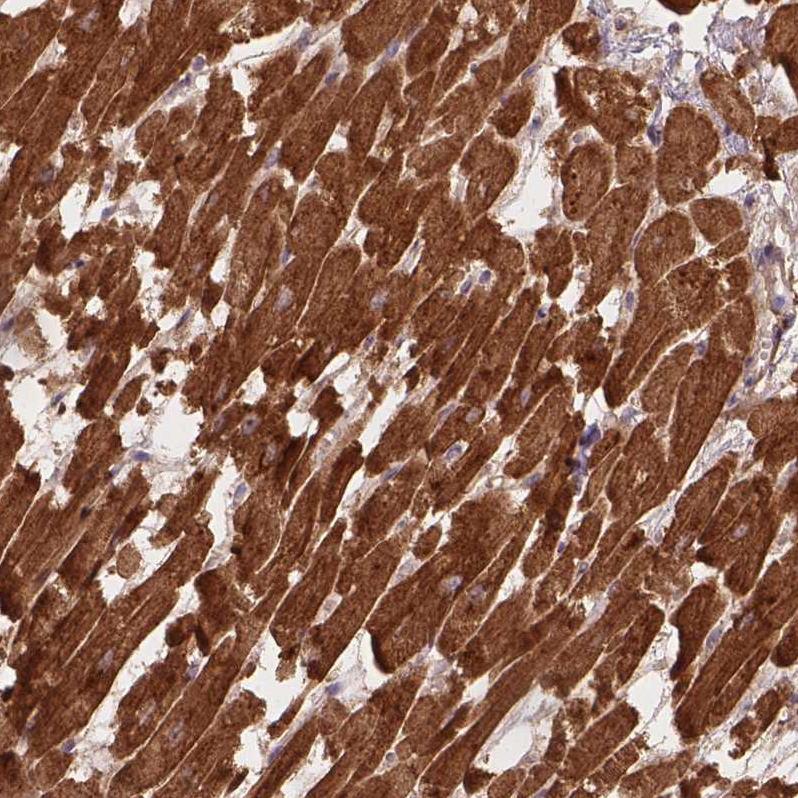

Immunohistochemical staining of human Testis shows strong membranous and cytoplasmic positivity in spermatogonia and cells in seminiferous ducts.